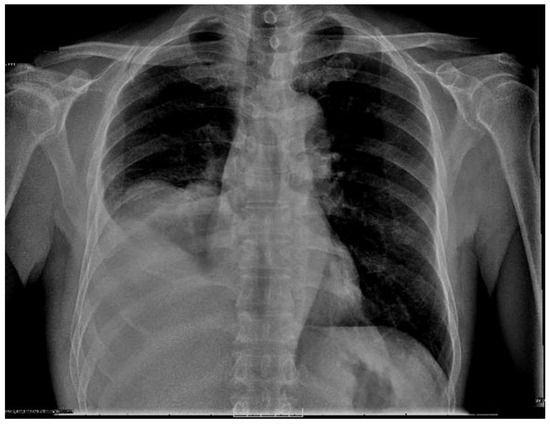

Tuberculous Empyema Presenting as a Persistent Chest Wall Mass: Case Report

by Jennifer Madeo, Rinal Patel, Wondwossen Gebre and Shadab Ahmed

Empyema necessitatis is an empyema that spreads outside of the pleural space involving the chest wall. Tuberculosis is the most common cause. It occurs in both immunocompetent and immunocompromised patients. Due to the long latency period and the paucity of symptoms, diagnosis can be challenging. Clinicians must have a high awareness of this disease, especially in patients from endemic regions. The disease is treatable with surgical and medical interventions. Failure to diagnose can lead to grave consequences for both the individual patient and public health. This is particularly true in endemic regions where controlling the spread of TB is challenging. We report a rare presentation of pulmonary tuberculosis in an otherwise healthy 72-year-old USA immigrant from Thailand. He presented with a painless, chronic chest wall swelling with minimal systemic symptoms. Imaging revealed empyema necessitatis. Histopathology could not give a definitive diagnosis because the tissue was too necrotic. Despite negative acid-fast staining, sputum cultures were positive for tuberculosis. The case presentation is followed by a brief review of the current relevant literature. This case highlights the importance of clinical suspicion and increased awareness for this silent but serious infection. Full article

Figure 1